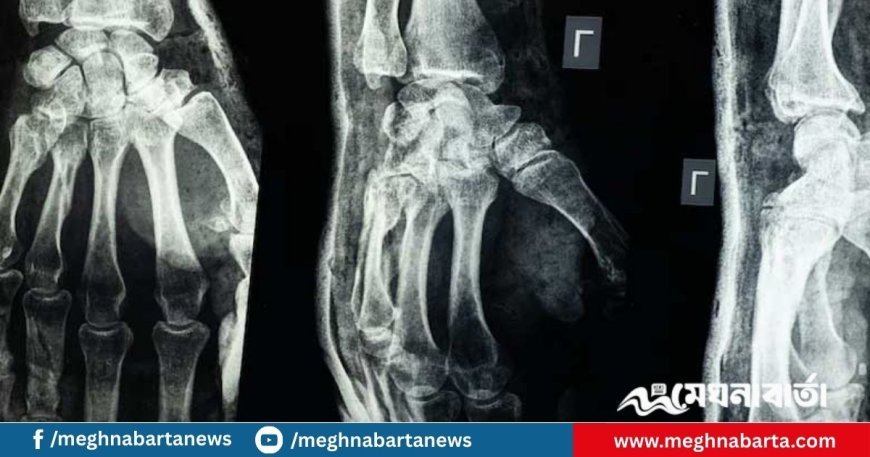

নিজস্ব প্রতিবেদক: অর্থোপেডিক চিকিৎসায় এক যুগান্তকারী সাফল্যের দাবি করেছেন চীনা গবেষকেরা। তারা উদ্ভাবন করেছেন চিকিৎসার উপযোগী এক ধরনের আঠা, যা মাত্র তিন মিনিটেই ভাঙা বা টুকরো টুকরো হাড় জোড়া দিতে সক্ষম। ‘বোন-০২’ নামের এই আঠা শরীরে জৈব উপায়ে শোষিত হয়, ফলে ধাতব সংযোজন (ইমপ্ল্যান্ট) ব্যবহারের প্রয়োজনীয়তা এবং এর কারণে সৃষ্ট দ্বিতীয়বার অস্ত্রোপচারের ঝুঁকি উল্লেখযোগ্যভাবে হ্রাস পায়। শনিবার (১৩ সেপ্টেম্বর) এনডিটিভিতে প্রকাশিত এক প্রতিবেদনে এসব তথ্য উঠে আসে।

এই আঠার মাধ্যমে মাত্র ২-৩ মিনিটেই হাড় জোড়া দেওয়া সম্ভব হয়। এমনকি রক্তপাত চলমান থাকলেও এটি তার কার্যকারিতা হারায় না। হাড় জোড়া লাগার পর এটি শরীরেই জৈবভাবে শোষিত হয়ে যায়, ফলে অপসারণের প্রয়োজন পড়ে না। ফলে রোগীকে দ্বিতীয়বার অস্ত্রোপচার বা ধাতব বস্তু সরানোর মতো ঝুঁকিতে পড়তে হয় না।

চীনের রাষ্ট্রীয় সংবাদমাধ্যম সিসিটিভি জানিয়েছে, এখন পর্যন্ত ১৫০ জনের বেশি রোগীর ওপর এই আঠা প্রয়োগ করে সফল ফলাফল পাওয়া গেছে। পরীক্ষাগারে দেখা গেছে, বোন-০২ দিয়ে জোড়া লাগানো হাড় ৪০০ পাউন্ডেরও বেশি চাপ সহ্য করতে পারে। এর পারস্পরিক চাপ সহনশীলতা (শেয়ার স্ট্রেংথ) প্রায় ০.৫ মেগাপ্যাসকেল (এমপিএ) এবং সংকোচন প্রতিরোধ ক্ষমতা প্রায় ১০ মেগাপ্যাসকেল—যা একে প্রচলিত ধাতব সংযোজনের কার্যকর বিকল্প হিসেবে ভাবার যথেষ্ট ভিত্তি দেয়।